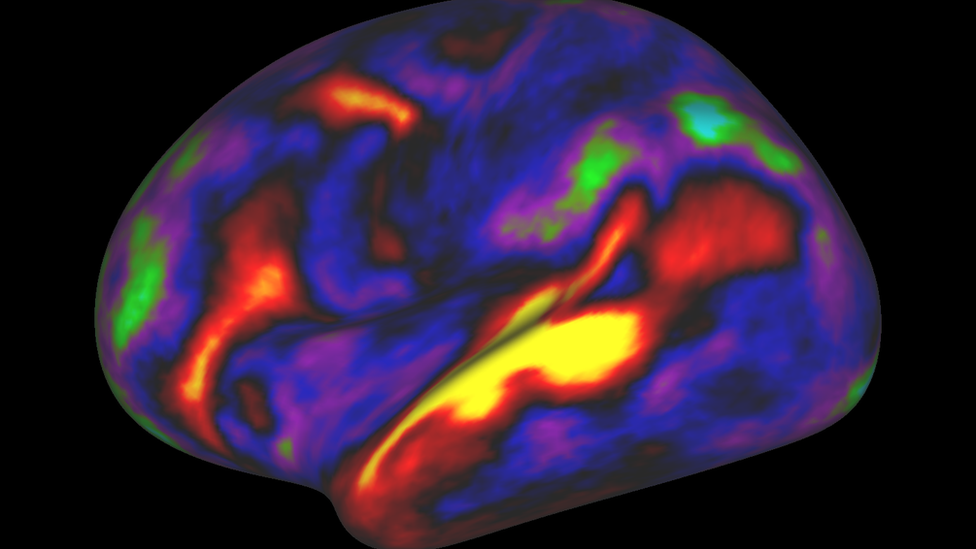

Both brain activity and its physical properties were used to create the map

The team used several different types of information, derived from lengthy scanning sessions of 210 people, to define the boundaries of 180 areas in each brain hemisphere.

To begin with, there were physical properties to consider - such as the amount of myelin, the substance which wraps nerve fibres, detected throughout the cortex; or variations in the folding and the thickness of the cortex.

But the researchers also looked at brain activity. Which regions were activated by particular tasks - reading as opposed to gambling, for example? And to what extent was activity in one area correlated and coordinated with activity elsewhere?